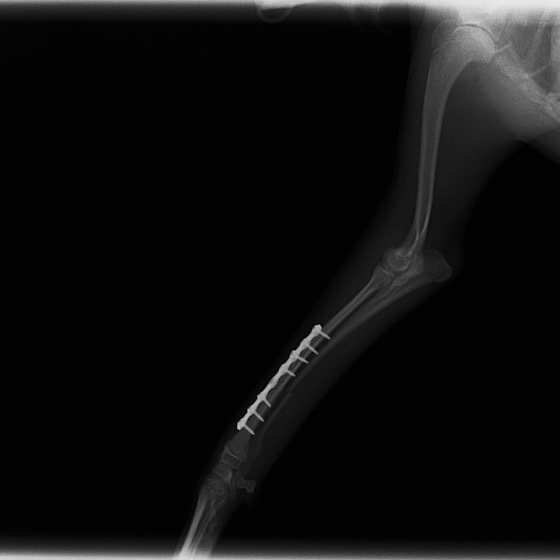

トイプードル 右遠位橈尺骨短斜骨折のALPSによる内固定